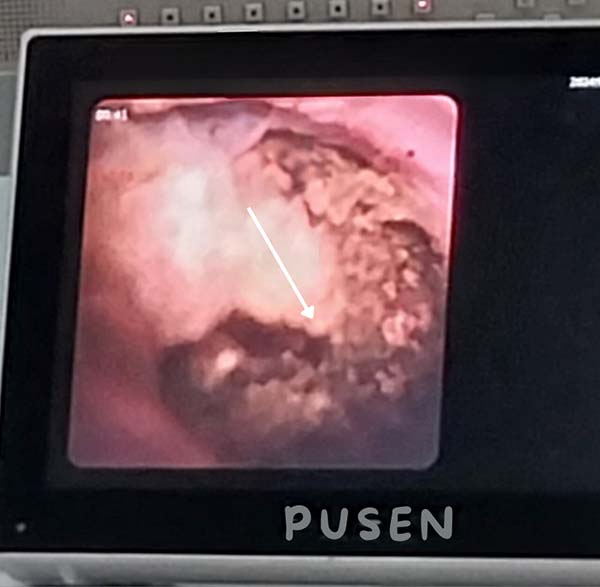

Quá trình bơm rửa đã lấy được nhiều sỏi nhỏ. Qua lỗ mở của ống mật chủ, các Bác sĩ dùng ống soi mềm để kiểm tra đường mật trong gan để đảm bảo không còn sỏi sót lại.

Sỏi đường mật nhánh gan trái. Ảnh: Bệnh viện cung cấp

Khi soi xuống ống mật chủ, các Bác sĩ phát hiện vẫn còn một viên sỏi khoảng 15mm bị kẹt ở đoạn cuối ống mật chủ và không thể lấy bằng dụng cụ Randal.

Kết hợp với máy tán sỏi laser, các Bác sĩ đã tán vụn viên sỏi ở đoạn cuối ống mật chủ, sau đó lấy hết sỏi và kiểm tra cơ vòng Oddi, thấy thông tốt và bệnh nhân đã được đặt thêm một ống dẫn lưu Kehr vào ống mật chủ.